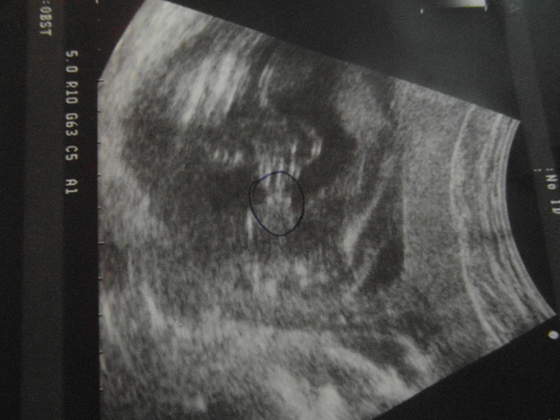

Gosheek, Madajka gratuluję zdrowych dzieciaczków. Super, że maleństwa tak pięknie się rozwijają. Dzisiaj podglądałam też na usg moje maleństwo. Wszystko ok, choć dzidziuś wstydliwy i nie lubi być podglądany. Nic między nóżkami nie wyrosło od ostatniej wizyty, także na 99,9% będzie Jagódka

Waży 236 gramów i z usg jest o tydzień większa niż z OM.